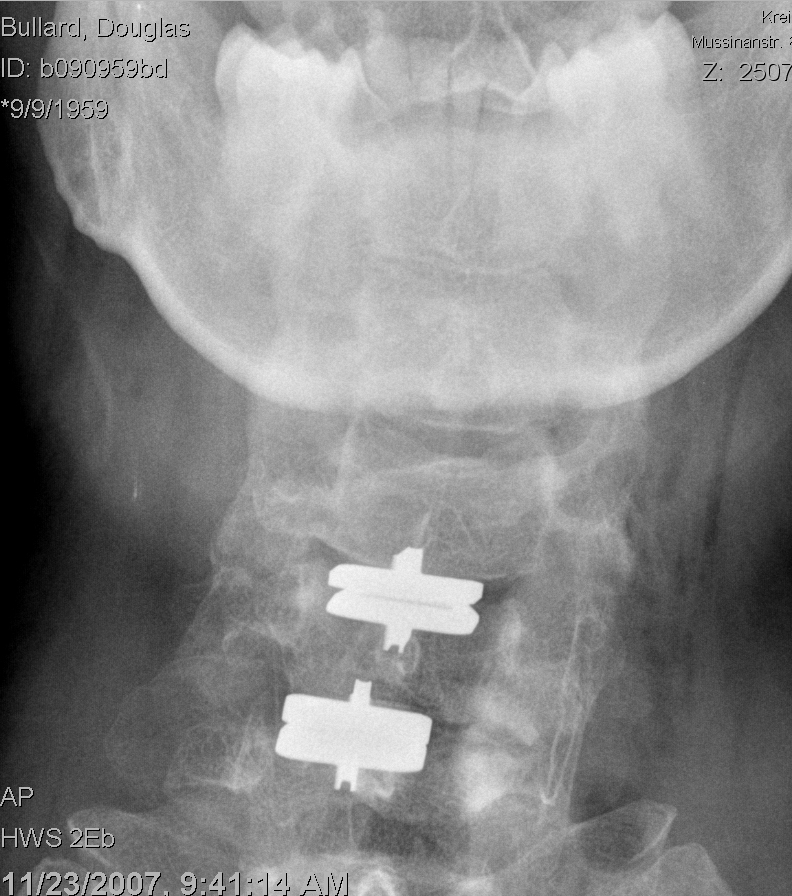

Post op front.jpg preview

Don't ask me why my neck's tilted like that - it's exactly the way the radiologist positioned my head for the shot.